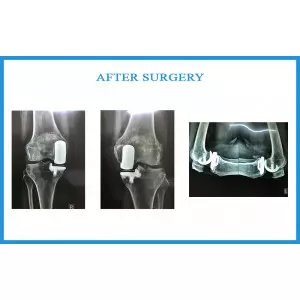

Shila Shah

Shila Shah Details